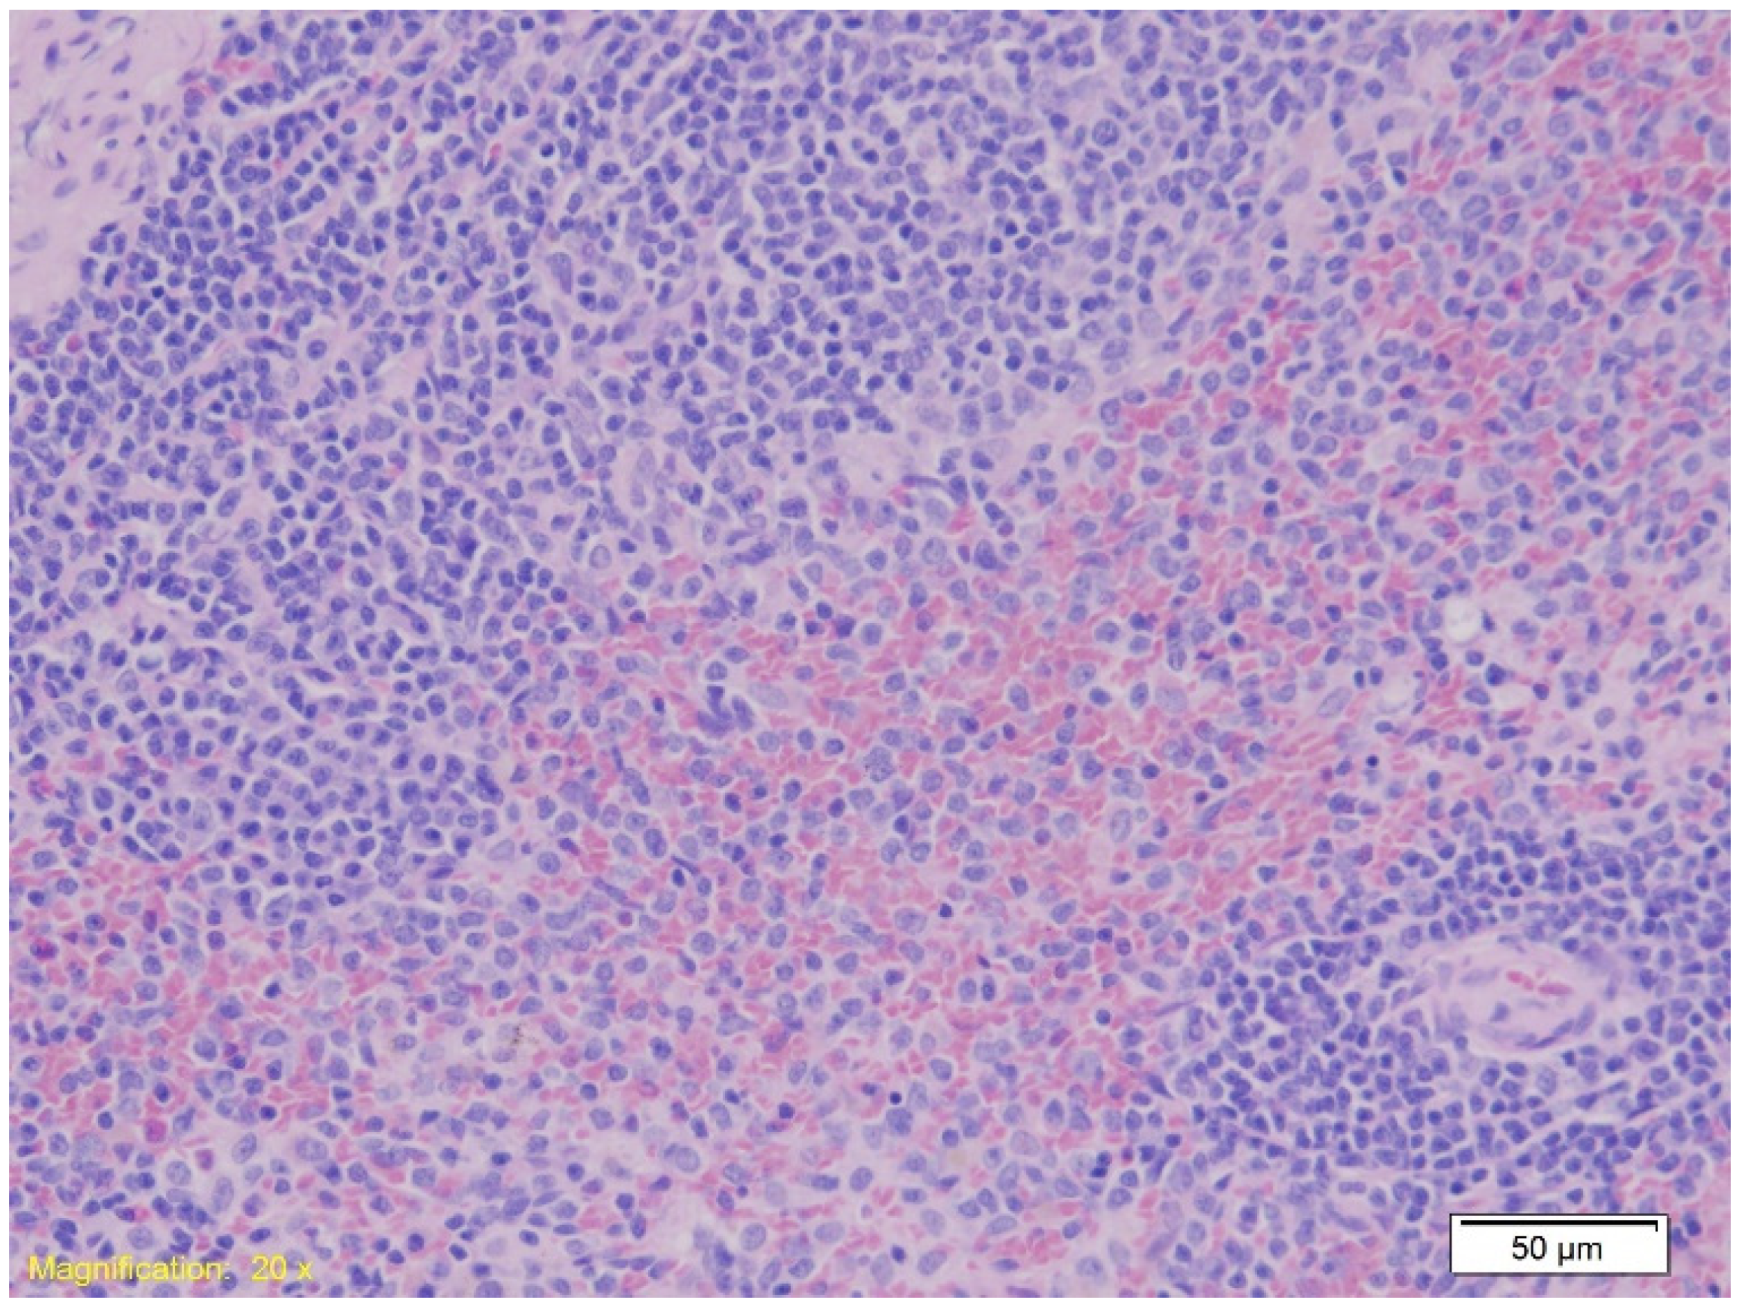

| Spleen | Preserved architecture with strong erythrocyte infiltration in red pulp. | Similar findings as Group K. | Similar findings as Group K. |